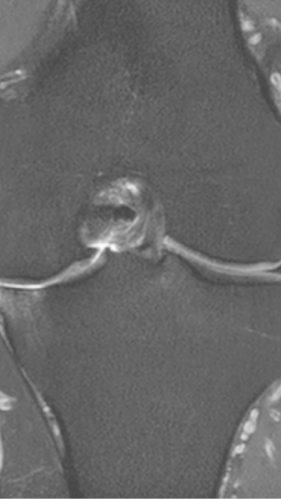

Рецидивирующий синовит коленного сустава

Излечение за 1 процедуру ФДТ РЕВИКСАН

Параметры изменяются в зависимости от процедуры

Дата публикации: 11.02.2026 10:52:38